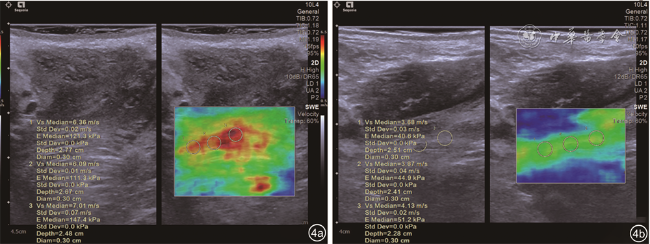

正常对照组和PFD组最大缩肛状态杨氏模量值及杨氏模量值差值比较,差异均有统计学意义(P均<0.05),2组静息状态杨氏模量值比较差异无统计学意义(P>0.05,表2图4)。

图 4 正常者(图a)和盆底功能障碍者(图b)耻骨直肠肌弹性图

本研究采用VTIQ技术对42例PFD组及52名正常对照者进行了分析。对照组最大缩肛状态杨氏模量值及杨氏模量值差值均大于PFD组,2组患者静息状态杨氏模量值差异无统计学意义。通过构建的ROC曲线显示,最大缩肛状态杨氏模量值和VTIQ技术测得的杨氏模量值差值诊断PFD的ROC曲线下面积分别为0.750和0.865,杨氏模量值差值曲线下面积大于最大缩肛状态杨氏模量值(Z=2.844,P<0.001),当杨氏模量值差值为28 kPa时,敏感度及特异度为71.43%、92.31%,杨氏模量值差值的特异度高于最大缩肛状态杨氏模量值,两者的敏感度相差不大,相比之下杨氏模量值差值在阴道分娩者产后PFD的预测更有价值,杨氏模量差值的改变更能体现盆底肌肌力功能的减弱。